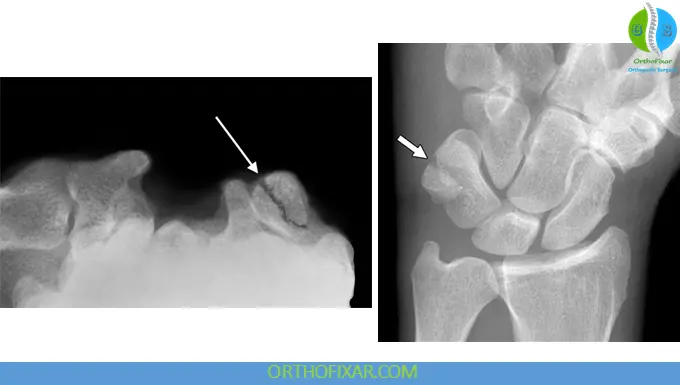

Imaging

Standard wrist radiographs often fail to clearly visualize the pisiform due to overlapping structures. Therefore:

- Carpal tunnel view or supinated oblique views improve detection

- CT scans provide high sensitivity for detecting fractures and displacement

- MRI may be useful in identifying associated soft tissue or ligamentous injuries

Evidence from radiologic studies highlights CT imaging as the gold standard when plain films are inconclusive.